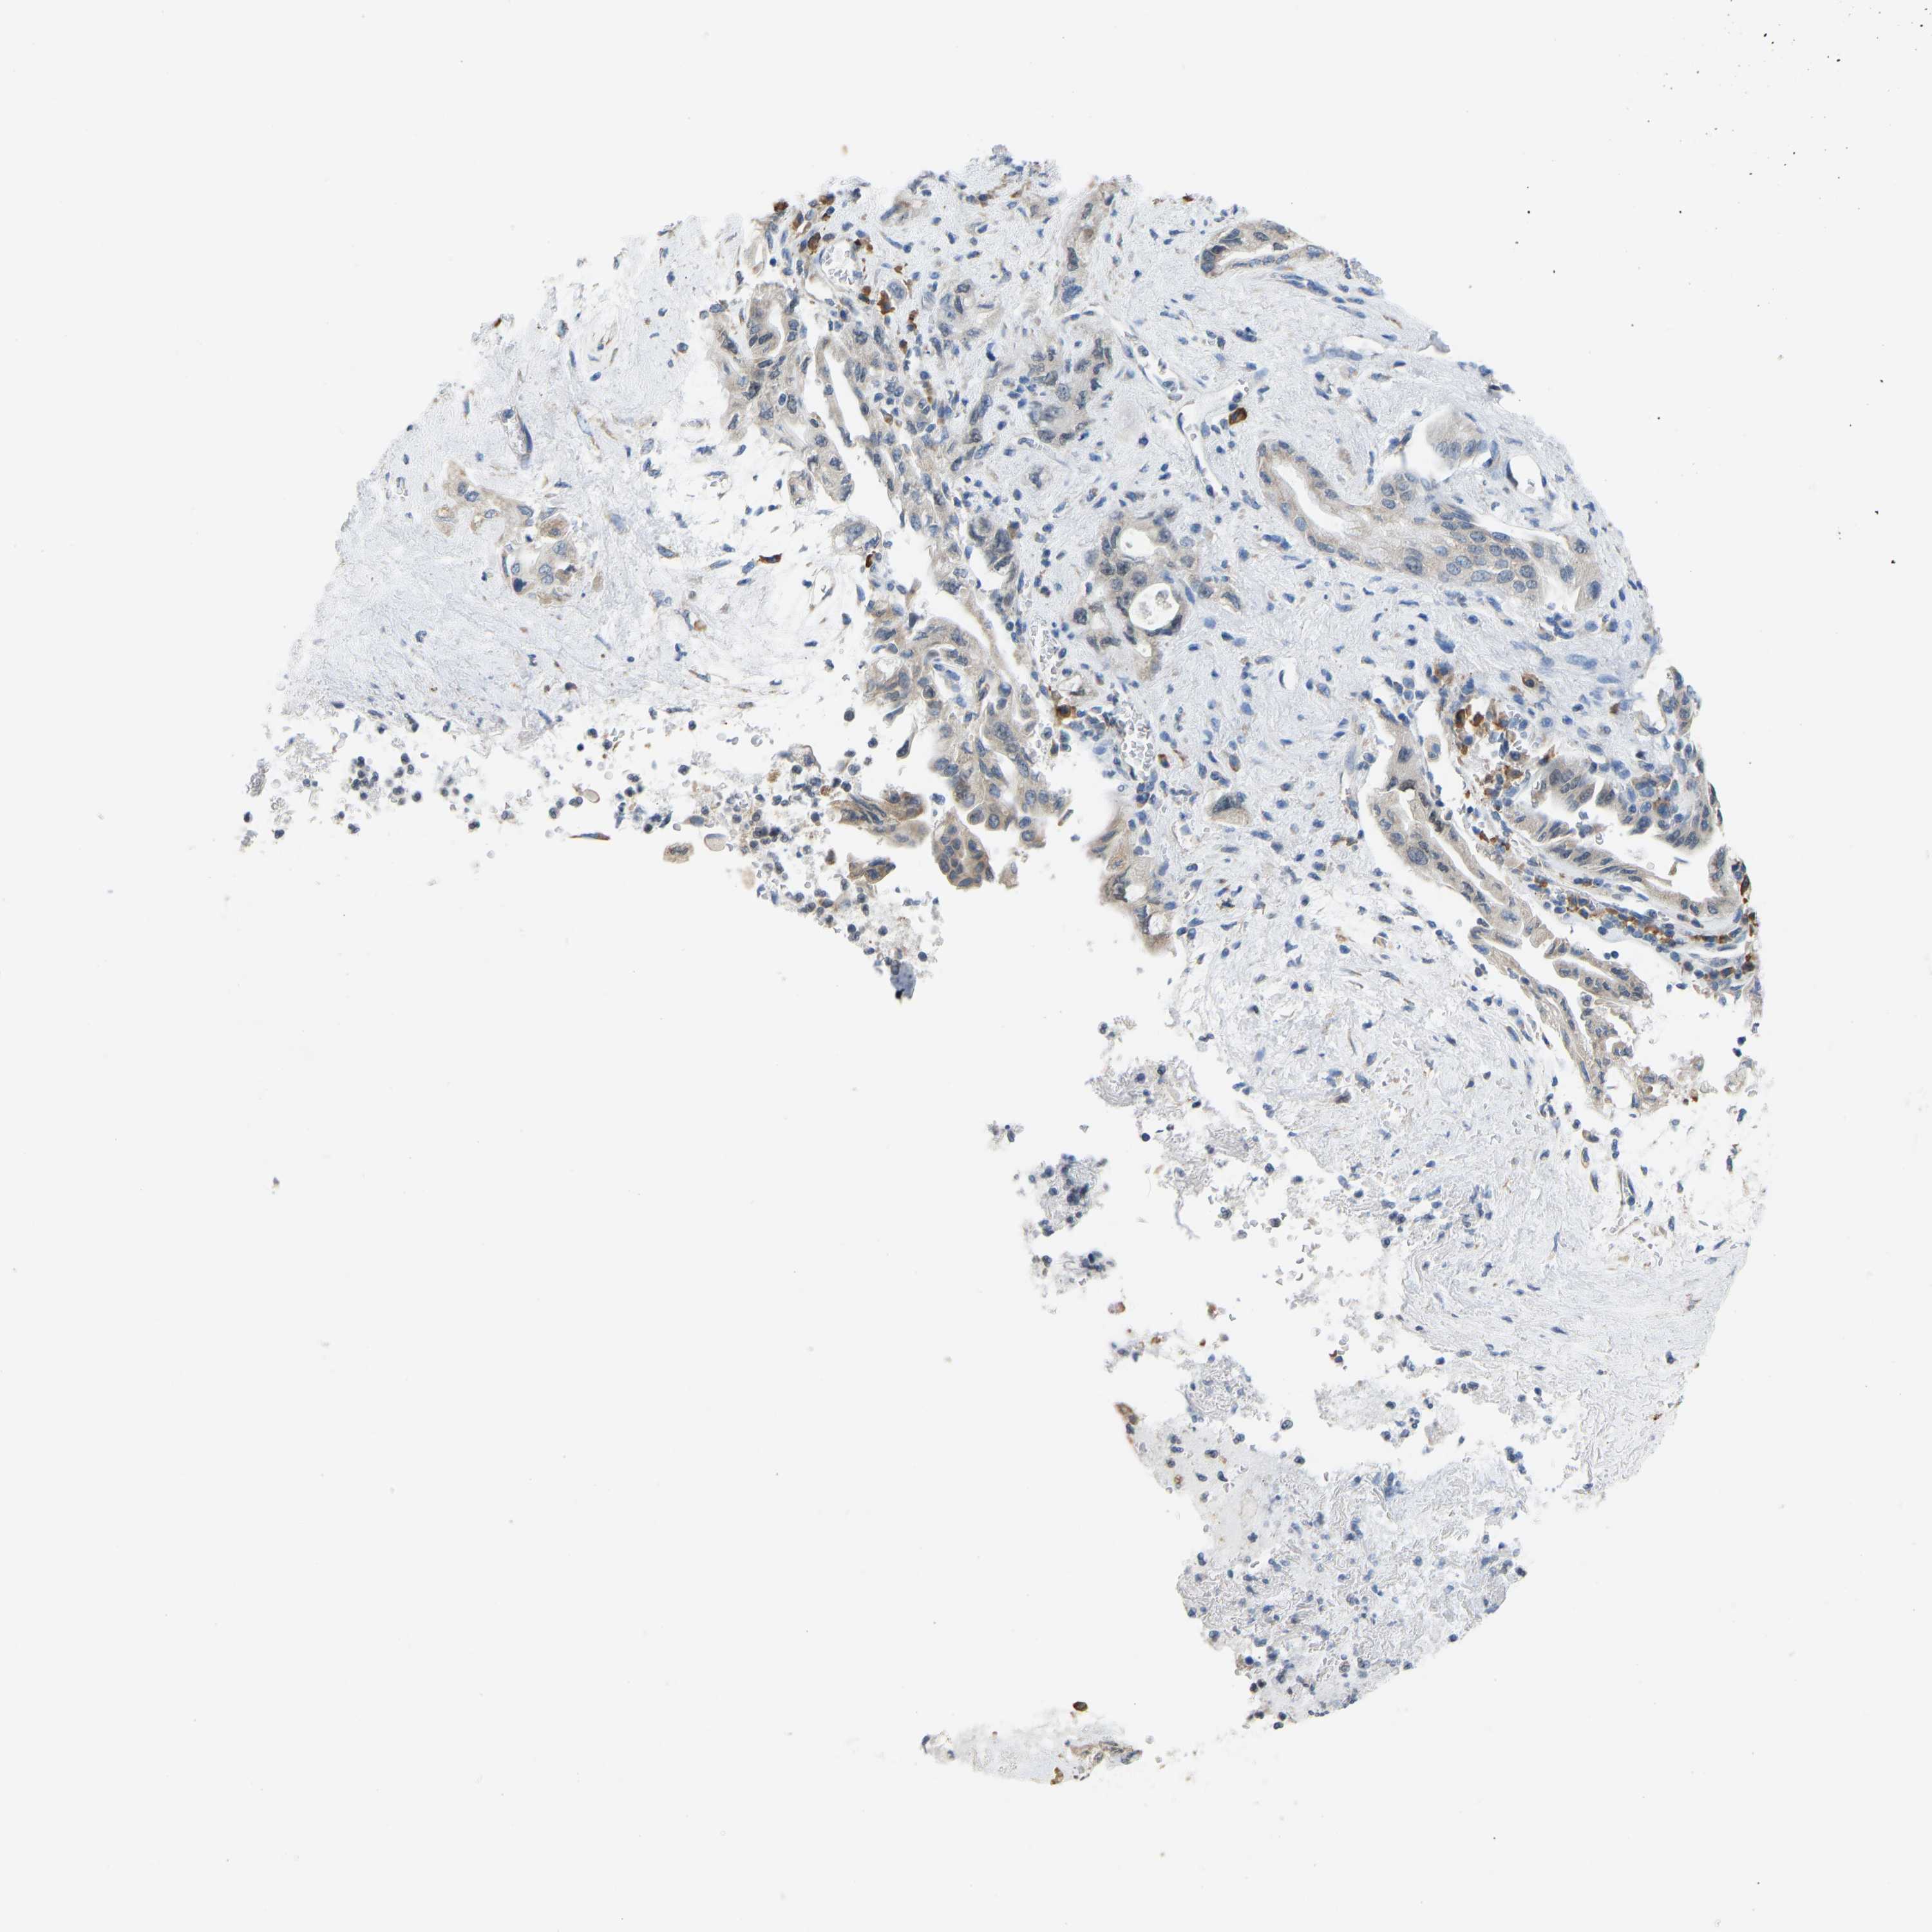

PANCREATIC CANCER - Protein expressioni

A mouse-over function shows sample information and annotation data. Click on an image to view it in a full screen mode. Samples can be filtered based on level of antibody staining by selecting one or several of the following categories: high, medium, low and not detected. The assay and annotation is described here.

Note that samples used for immunohistochemistry by the Human Protein Atlas do not correspond to samples in the TCGA dataset.

Antibody stainingi

Antibody staining in the annotated cell types in the current human tissue is reported as not detected, low, medium, or high, based on conventional immunohistochemistry profiling in selected tissues. This score is based on the combination of the staining intensity and fraction of stained cells.

Each image is clickable and will lead to virtual microscopy that enables deeper exploration of all samples and also displays staining intensity scores, fraction scores and subcellular localization as well as patient and tissue information for each sample.

Antibody HPA000660

Antibody HPA017929

Staining

High

Medium

Low

Not detected

Intensity

Strong

Moderate

Weak

Negative

Quantity

>75%

75%-25%

<25%

None

Location

Nuclear

Cytoplasmic/membranous

Cytoplasmic/membranous,nuclear

Adenocarcinoma, NOS